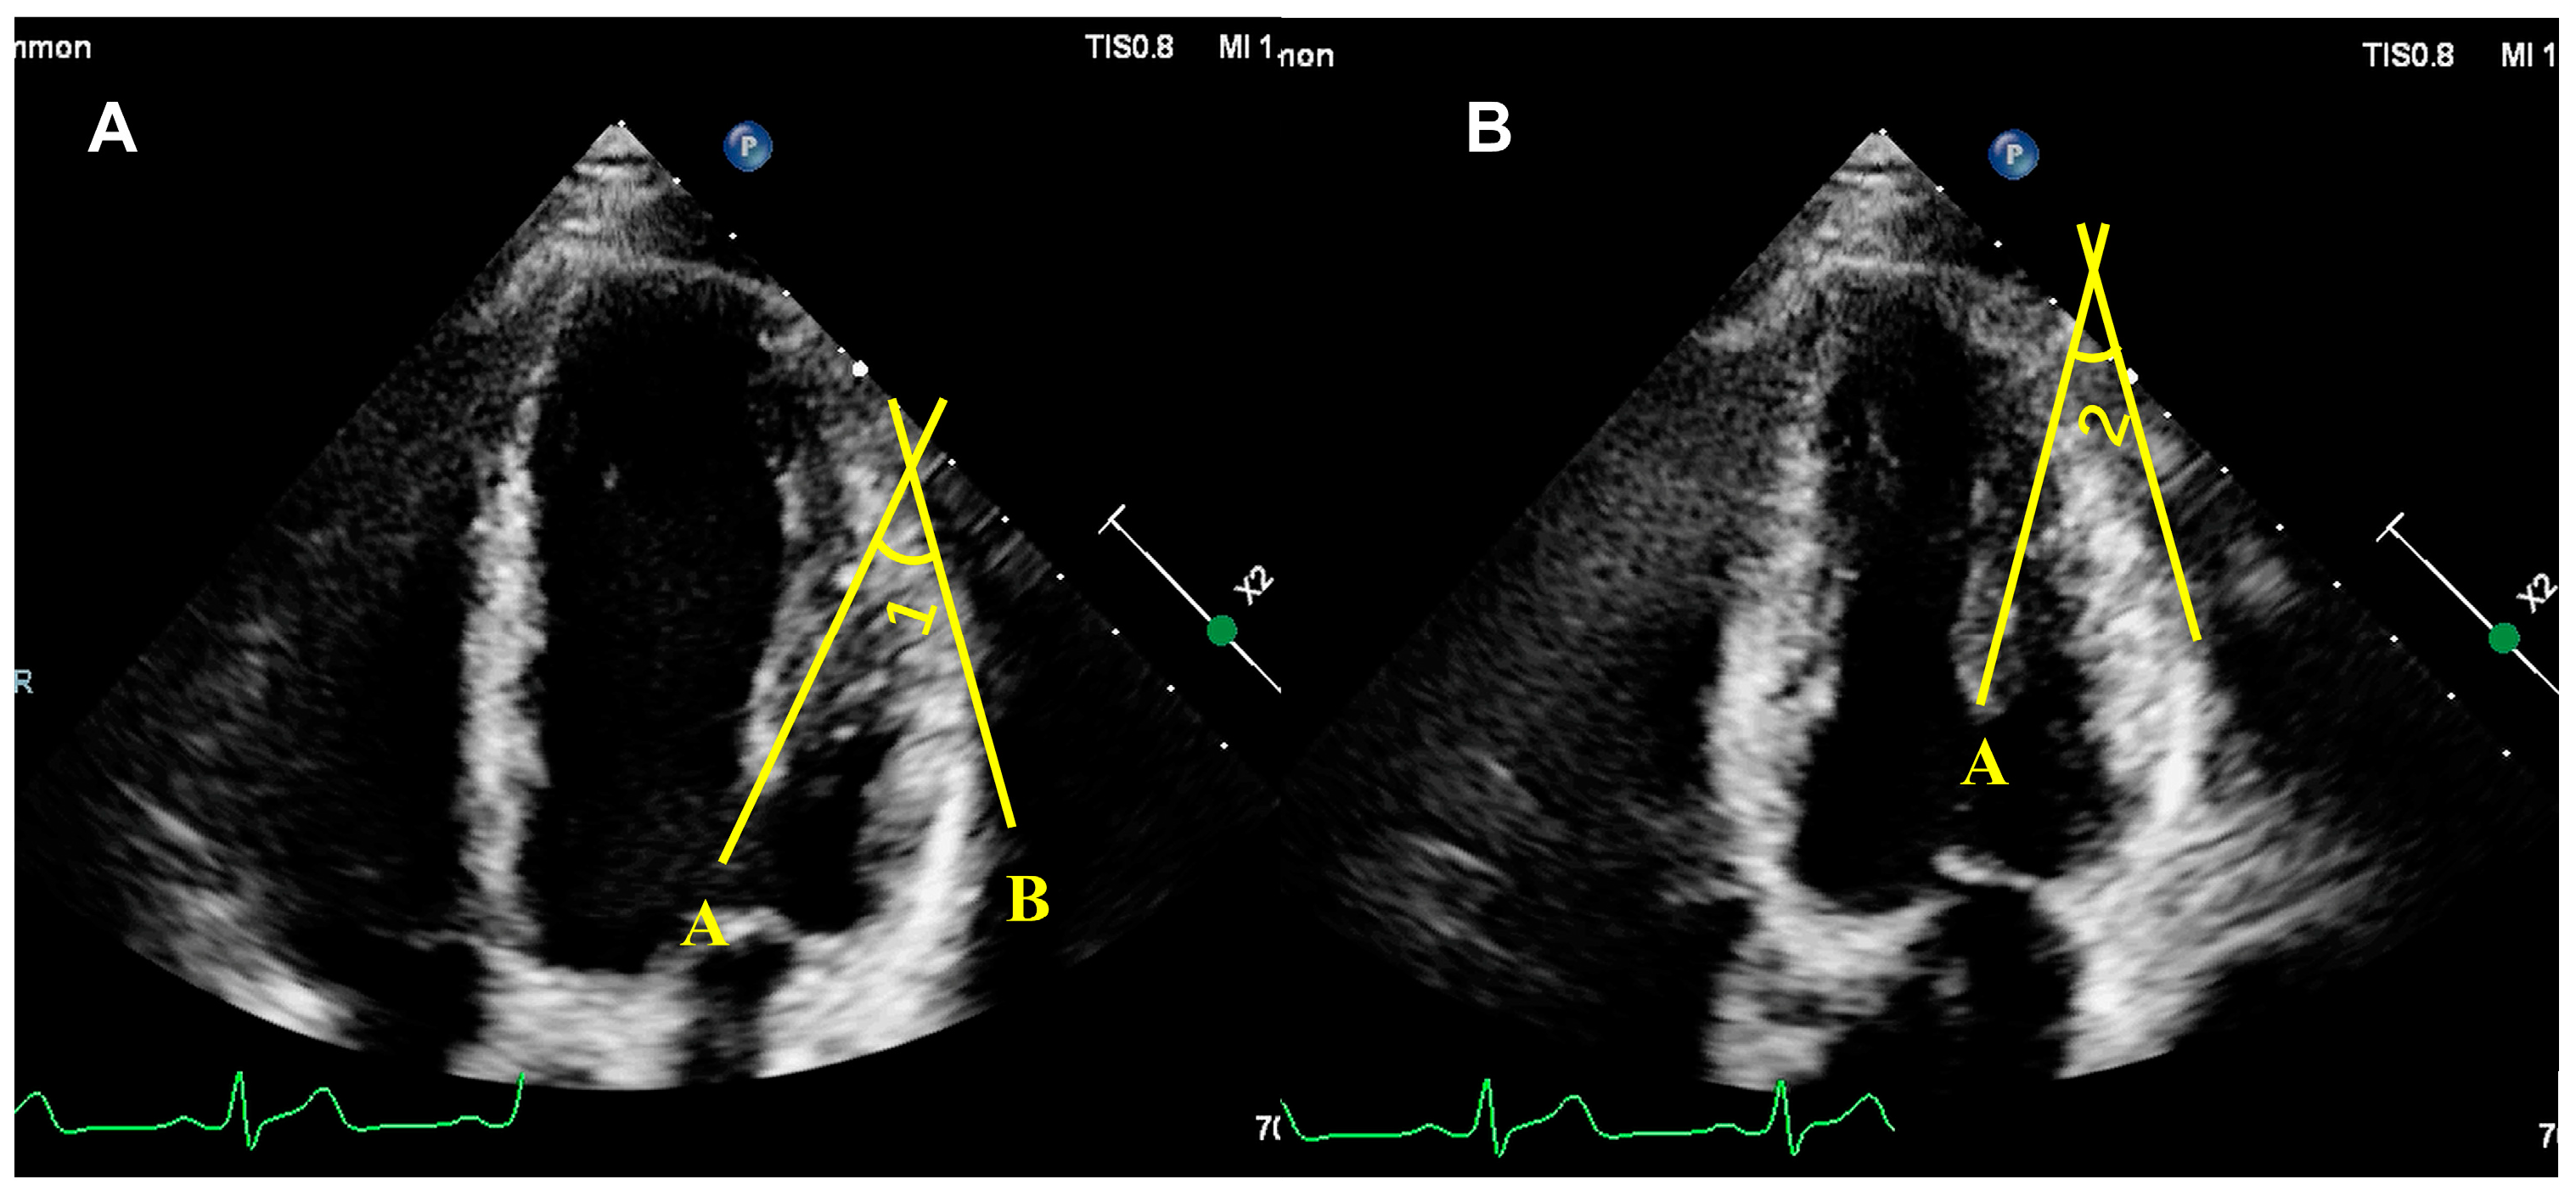

5.1. Assessment of PM Structure

5.2.2. Quantitative Assessment of PM Function